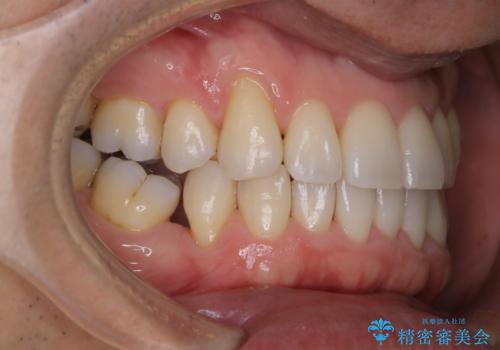

紅茶のステインをきれいにしたい

- 毎日紅茶を飲むため、歯のステインが気になるためキレイにしたいとのことでした。

PMTC60分コースを行いました。